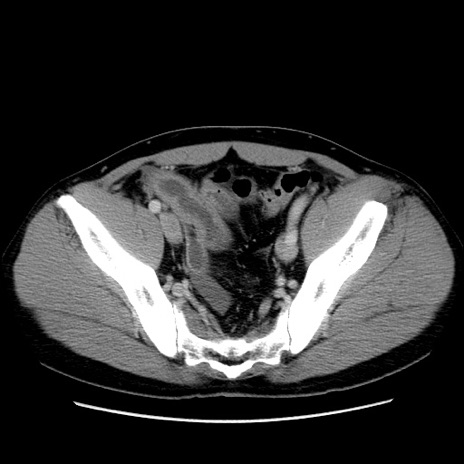

冠状断像